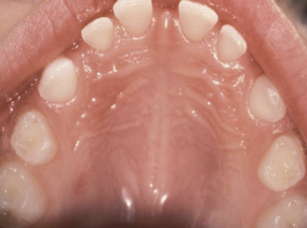

intra-oral presentation of congenital syphilis;1st molars develop irregular nodules of enamel on occlusal surface

mulberry molars